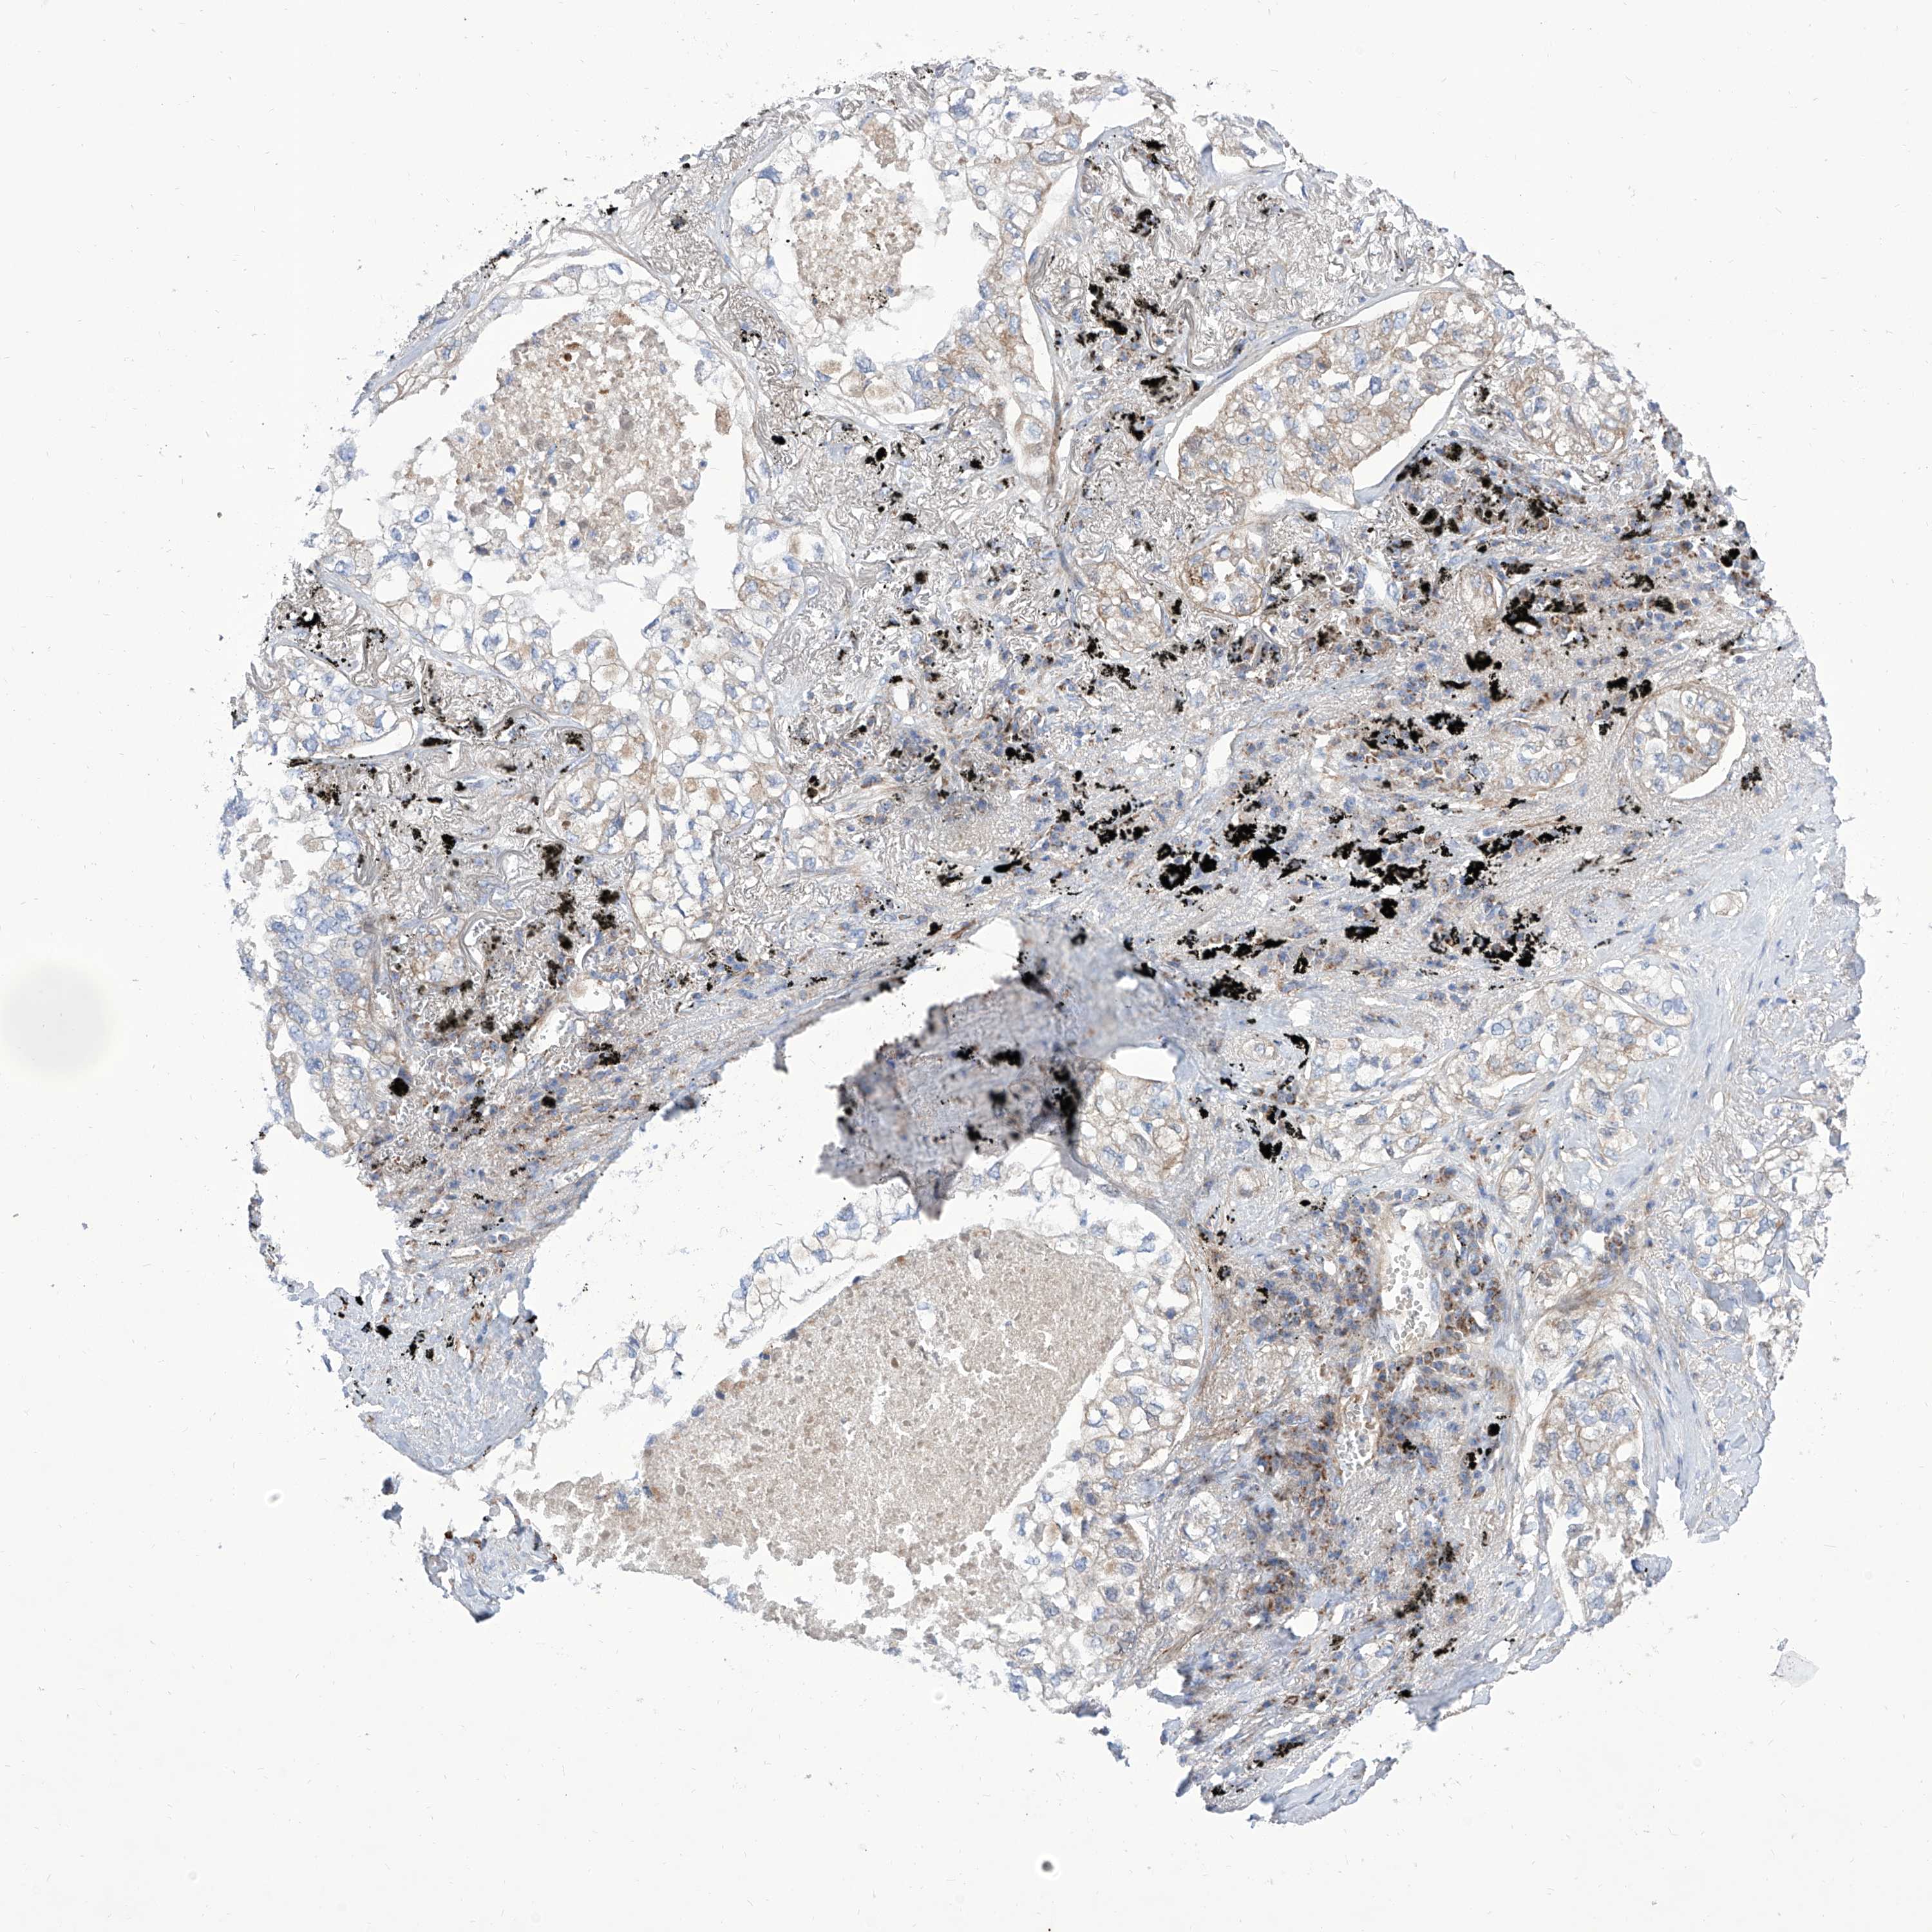

CANCER LUNG CANCER Show tissue menu

LUAD TCGA LUAD VALIDATION LUSC TCGA LUSC VALIDATION PROTEIN LUAD CPTAC PROTEIN LUSC CPTAC PROTEIN EXPRESSION

ANTIBODIES

AND

VALIDATION